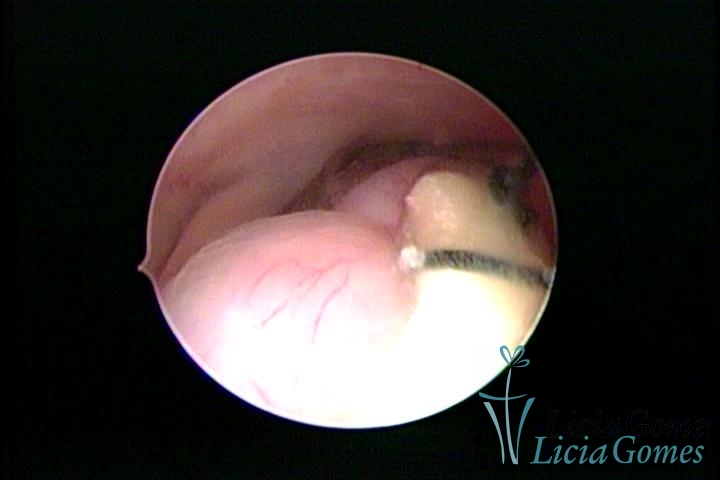

Cicatriz de cesárea com fio de sutura, não absorvido, como corpo estranho

×